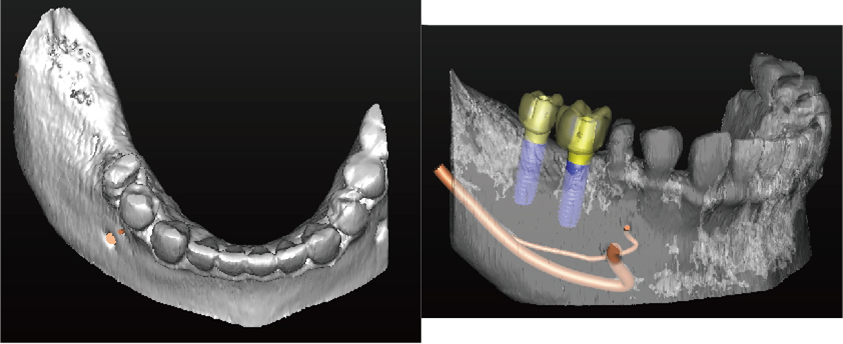

噛み合わせ、骨の厚みや神経の走行からみて理想的なインプラントの位置を決定

コンピューターガイデッド インプラント治療とは

「シンプラント プロ」で計画されたシミュレーションデータからサージガイドを作製します。

作製されたサージガイドをお口の中に装着して手術を行うことにより、計画した位置をお口の中に正確にトランスファーしてインプラント手術することができます。

サージガイドを使用することで、狭く小さいお口の中や手術しにくい奥歯でも精度の高い正確なインプラント治療が行うことが可能です

理想的な位置に計画された3DデータからCAD/CAMで高精度なサージガイドを作ります